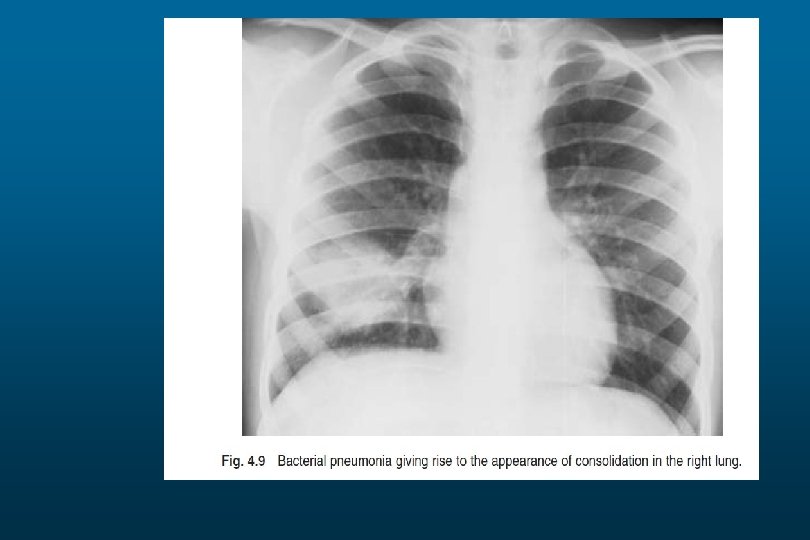

Right Upper Lobe Pneumonia

Right lower Lobe Pneumonia